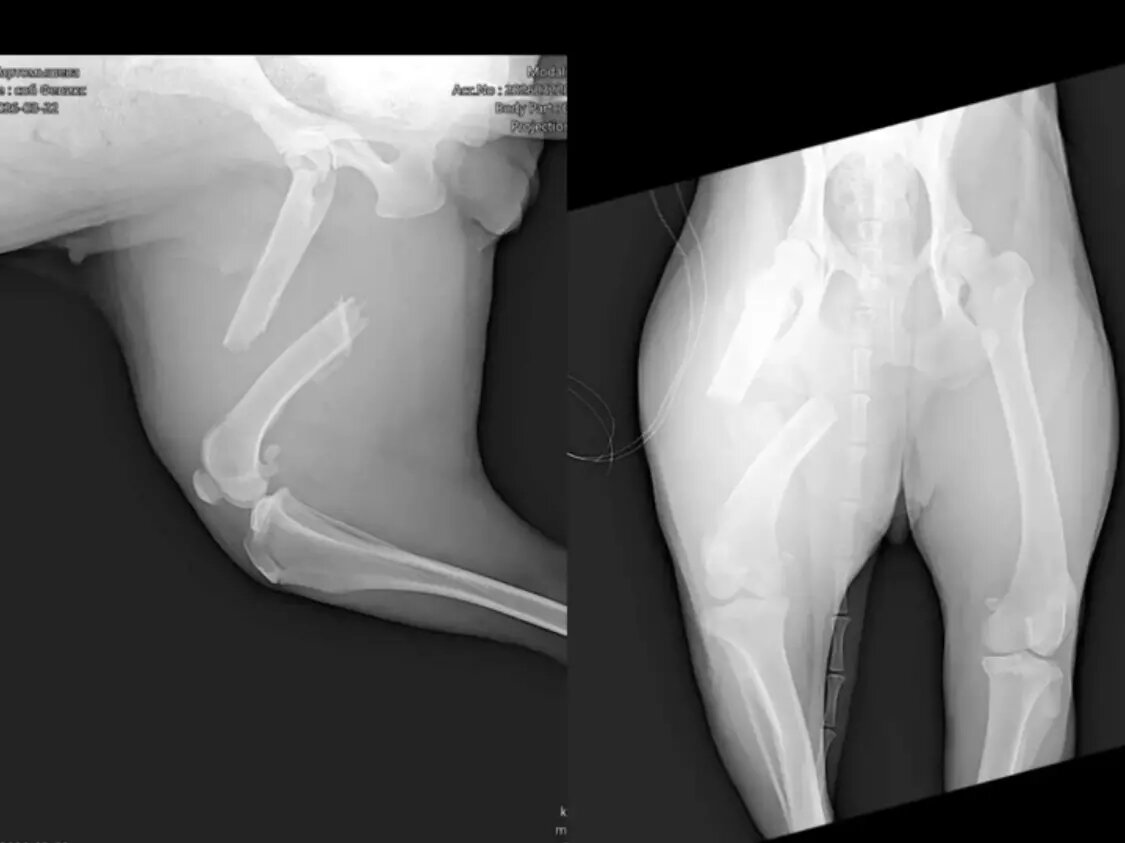

Сложную операцию провели псу из Азова с тяжелым переломом берцовой кости

Травмированное животное отвезли в клинику Ростова. Врачи шокировали волонтеров — уже долгое время Сэнди ходила со сложным переломом берцовой кости с большим смещением.

Днем 25 марта псу провели операцию, которая длилась целых пять часов.

- Все осложнялось тем, что перелом Сэнди получила около трех недель назад, - уточнили в приюте. - Это стало понятно во время операции, когда доктор увидел, что все обросло костно-мозольной тканью.

Сэнди уже даже стала опираться на эту лапу фактически без опоры на кость. Был риск, что лапу придётся удалить, но врач с огромным трудом освободил кости для наложения металлоконструкции.

Врачи смогли буквально по кусочкам «собрать перелом» на реконструктивную пластину. Врачи и волонтеры надеются на восстановление кровообращения в тканях.